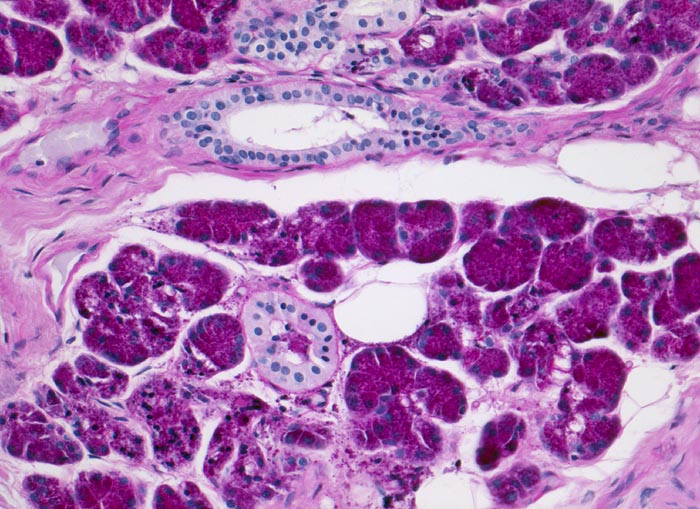

Azinuszellkarzinom der Glandula Parotis

Die zytologische Diagnose des Azinuszellkarzinoms basiert auf dem Nachweis von Azinuszellen bei gleichzeitigem Fehlen von Gangstrukturen. Die Tumorzellen gleichen normalen serösen Azinuszellen. Zytoplasma ist reichlich vorhanden und variiert von schaumig bis grobgranulär. Degranulierte Zellen erscheinen schaumig, Zellen mit dichtgepackten Granula gleichen Onkozyten. Die Granula der Onkozyten sind aber feiner. Die Tumorzellkerne sind meist ziemlich wenig atypisch und monomorph. Das Chromatin variiert von fein bis mittelgrob. Intranukleäre Zytoplasmaeinschlüsse kommen vor. Die oft vorhandenen zahlreichen Nacktkerne müssen von ebenfalls oft vorhandenen Lymphozyten abgegrenzt werden. Die meist hoch differenzierten Tumoren können mit normaler Speicheldrüse verwechselt werden.